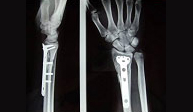

The wrist fracture often requires reduction of bone fragments to the anatomic position. The immediate reduction performed in the ER needs followed-up care to make sure there is no further displacement. Older patients usually benefit from conservative treatment with immobilization for 8 weeks. In young patients the displacement is usually difficult to manage with cast immobilization and surgery is needed making a small operation for platin and screwing the fragments. The patient may return to normal activity as quickly as possible and with limited risk of complications.